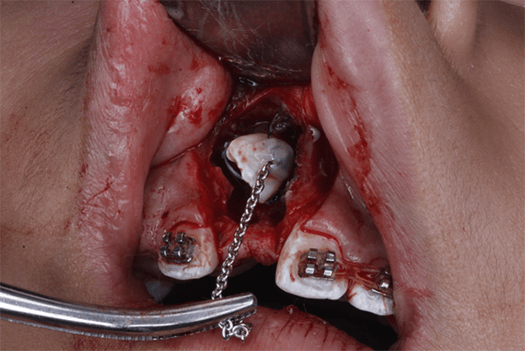

Dentro del procedimiento quirúrgico se colocó anestesia infiltrativa supraperióstica en la región vestibular y palatina del diente 1.1, se realizó incisión combinando abordaje de frenectomia labial y supracrestal con diseño romboidal con descargas en región de dientes 21 y 12, exposición de diente 11 incluido mediante osteotomía con fresa 702 para posterior colocación de botón para traccion (Fig. 12 y 13). Se programó cita de control en 8 días y retiro de puntos en 15 días desde el día de la intervención quirúrgica.

Fig 12. Ventana Quirúrgica y frenectomía labial

Fig 13. Fotografía colocación de botón cóncavo con cadeneta para tracción